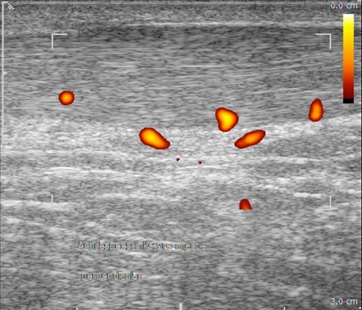

Neovascularisation and adjacent nerve infiltration in/around the Achilles tendon is of increasing interest, as this is usually seen in patients with tendinopathy and mostly absent in healthy tendons. Neovessels are suggested to play a role in the chronicity of symptoms.

But was the procedure performed successful? Doppler flow to visualise neovascularisation disappeared in 79% of the patients after the injection procedure in the HVI group, compared to 30% in the placebo group.